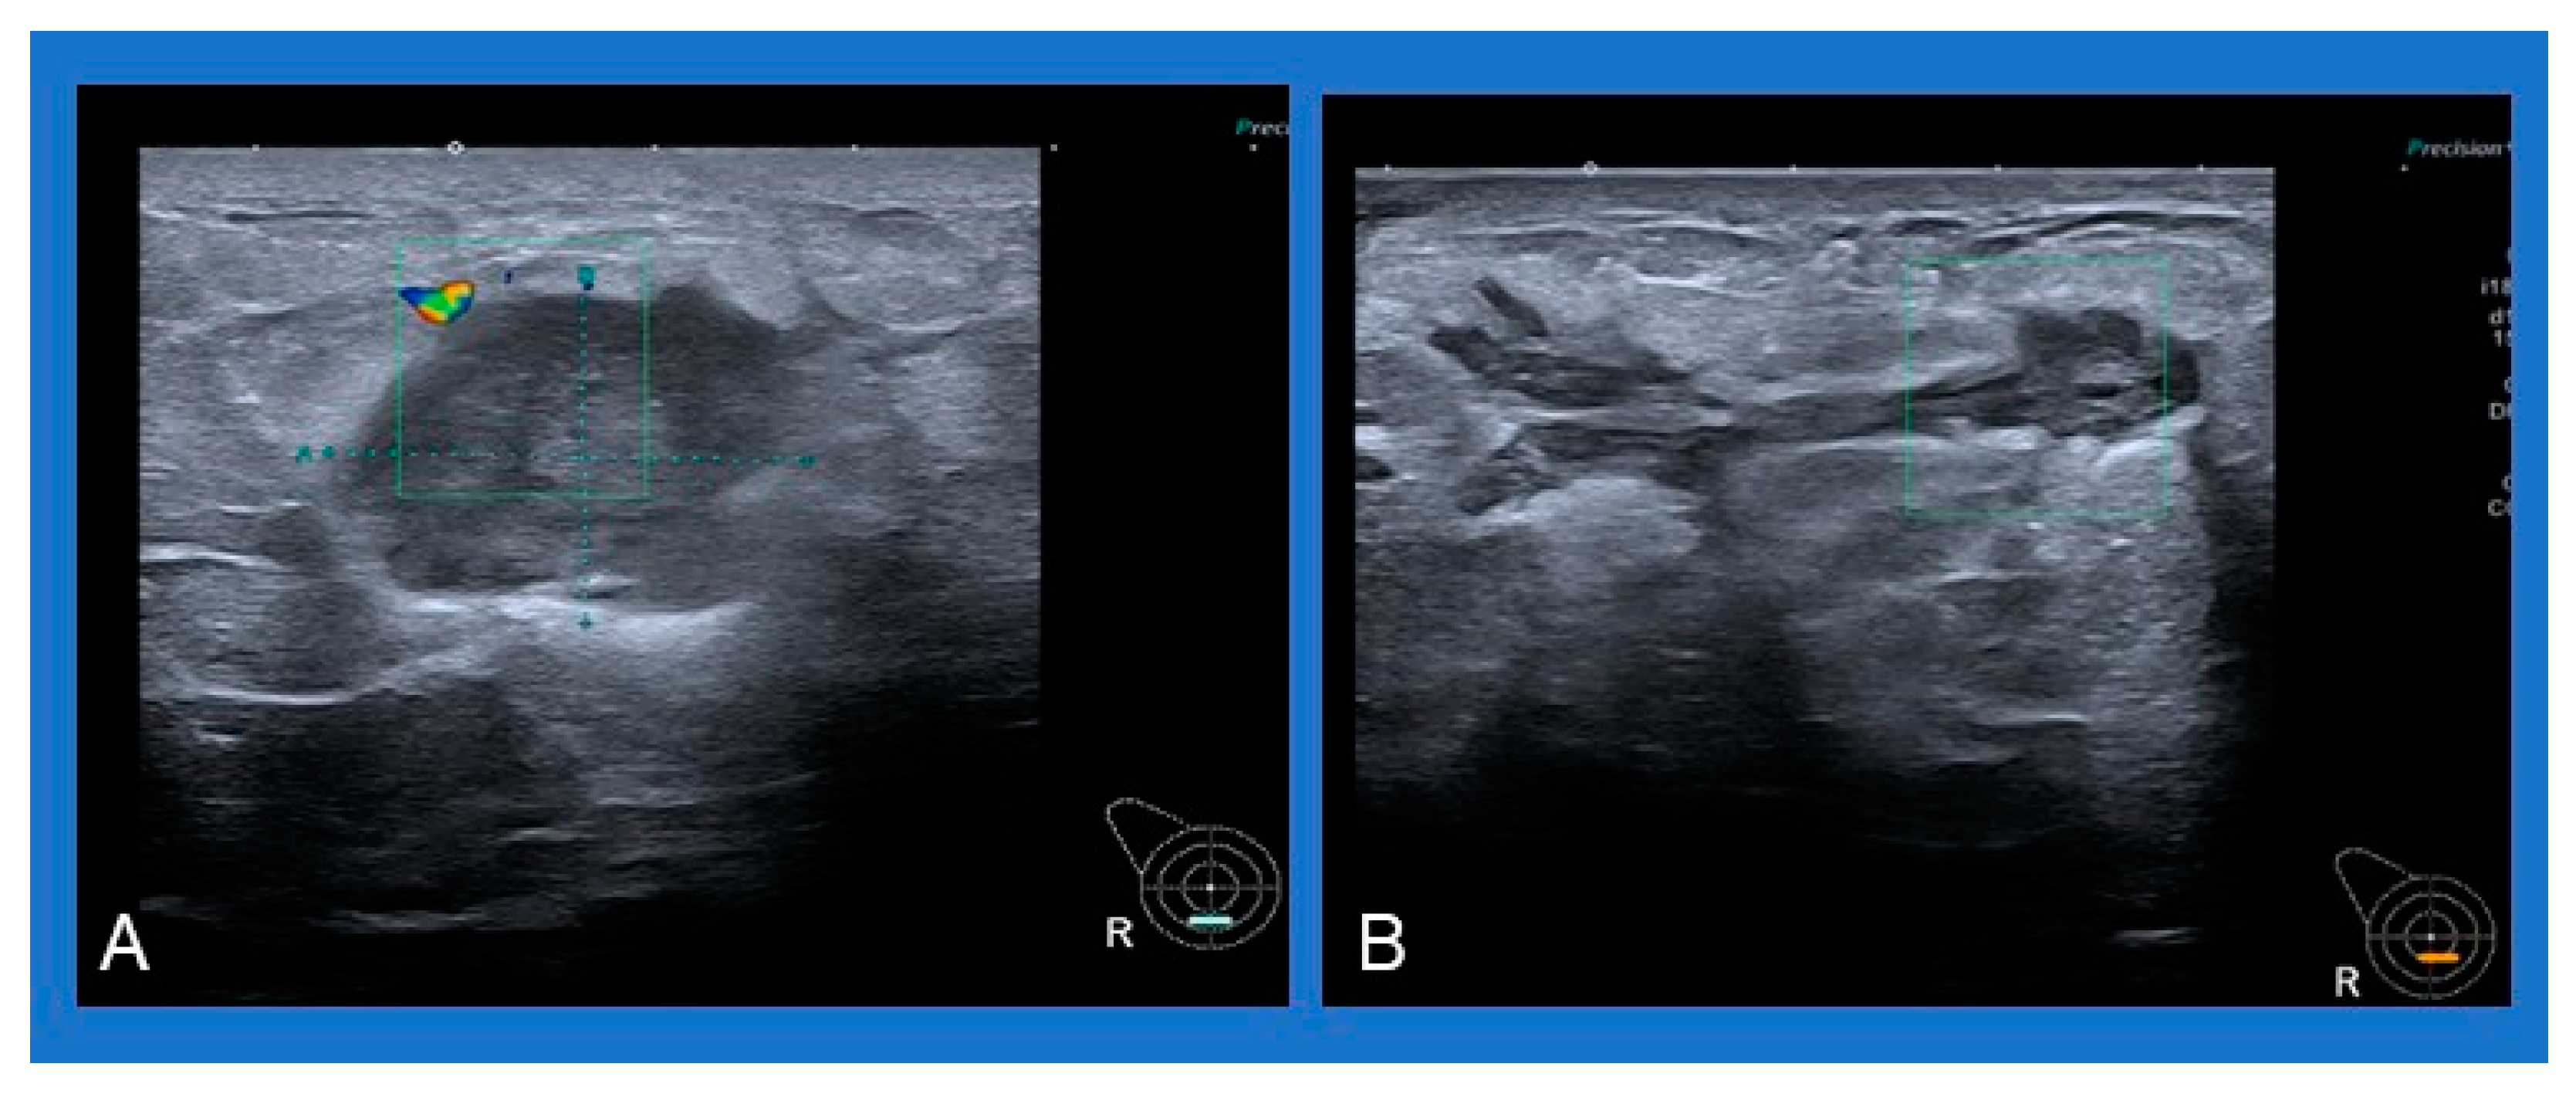

- Alikhassi, A.; Azizi, F.; Ensani, F. Imaging features of granulomatous mastitis in 36 patients with new sonographic signs. J. Ultrasound 2020, 23, 61–68. [Google Scholar] [CrossRef]

- Pluguez-Turull, C.W.; Nanyes, J.E.; Quintero, C.J.; Alizai, H.; Mais, D.D.; Kist, K.A.; Dornbluth, N.C. Idiopathic Granulomatous Mastitis: Manifestations at Multimodality Imaging and Pitfalls. Radiographics 2018, 38, 330–356. [Google Scholar] [CrossRef]

- Sripathi, S.; Ayachit, A.; Bala, A.; Kadavigere, R.; Kumar, S. Idiopathic granulomatous mastitis: A diagnostic dilemma for the breast radiologist. Insights Imaging 2016, 7, 523–529. [Google Scholar] [CrossRef]

- Yildiz, S.; Aralasmak, A.; Kadioglu, H.; Toprak, H.; Yetis, H.; Gucin, Z.; Kocakoc, E. Radiologic findings of idiopathic granulomatous mastitis. Med. Ultrason. 2015, 17, 39–44. [Google Scholar] [CrossRef] [PubMed]